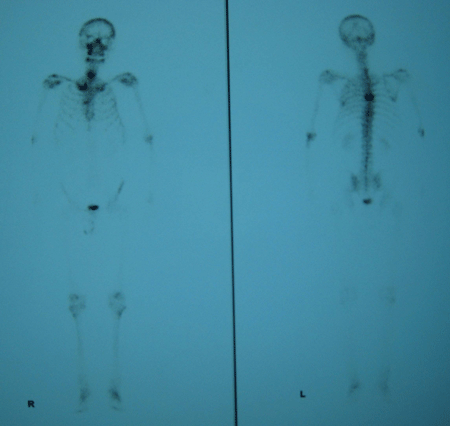

骨扫描正常报告单图片,骨扫描报告单图片

9g/l; 骨扫描:右侧第1,2,6,7,9肋骨及左侧第1,7,8,9肋骨多发点状放射

骨扫描报告单图片

正常骨扫描图片

正常人全身骨扫描图片

骨扫描显示骨转移图片

全身骨扫描图片

肺癌骨转移骨扫描图片